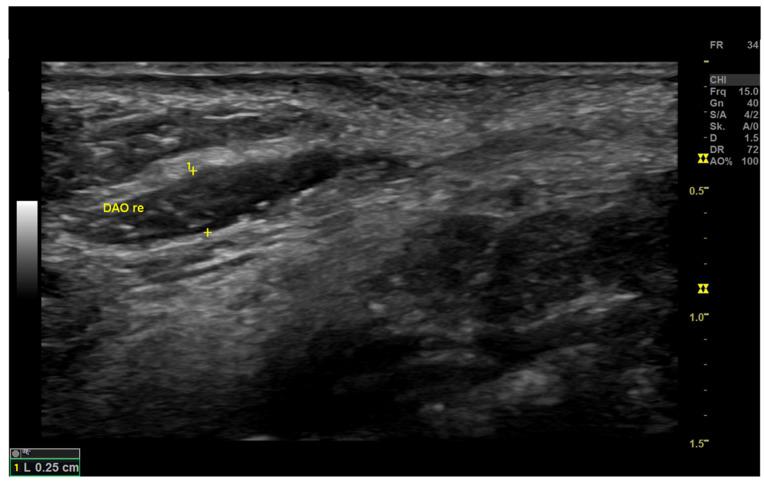

From December 2020 to April 2021, 20 patients with unilateral synkinesis underwent HRUS. All HRUS examinations were performed by the first author using US devices with linear multifrequency transducers of 4-18 MHz, including a LOGIQ E9 and a LOGIQ S7 XDclear (GE Healthcare; Milwaukee, WI, USA), as well as Philips Affinity 50G (Philips Health Systems; Eindhoven, the Netherlands).

Higher-frequency and multifrequency linear probes ≥15 MHz provided superior imaging qualities. The selection of the preset program Small Parts, Breast or Thyroid was linked with a more detailed contrast of the imaging morphology of facial tissue layers. Frequency (Frq) = 15 MHz, Gain (Gn) = 25-35 db, Depth (D) = 1-1.5 cm, and Focus (F) = 0.5 cm enhanced the image quality and assessability.